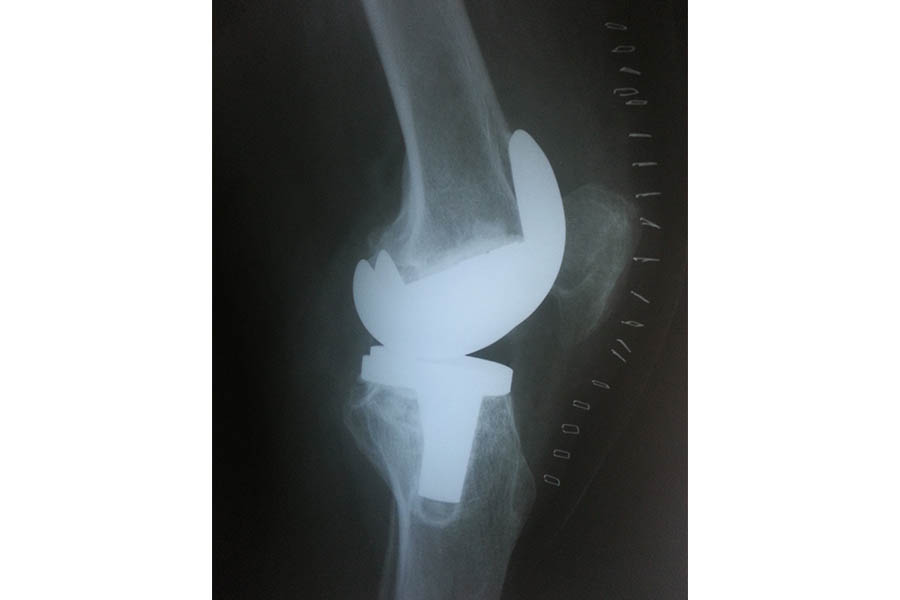

Total Elbow Replacement

Case 1